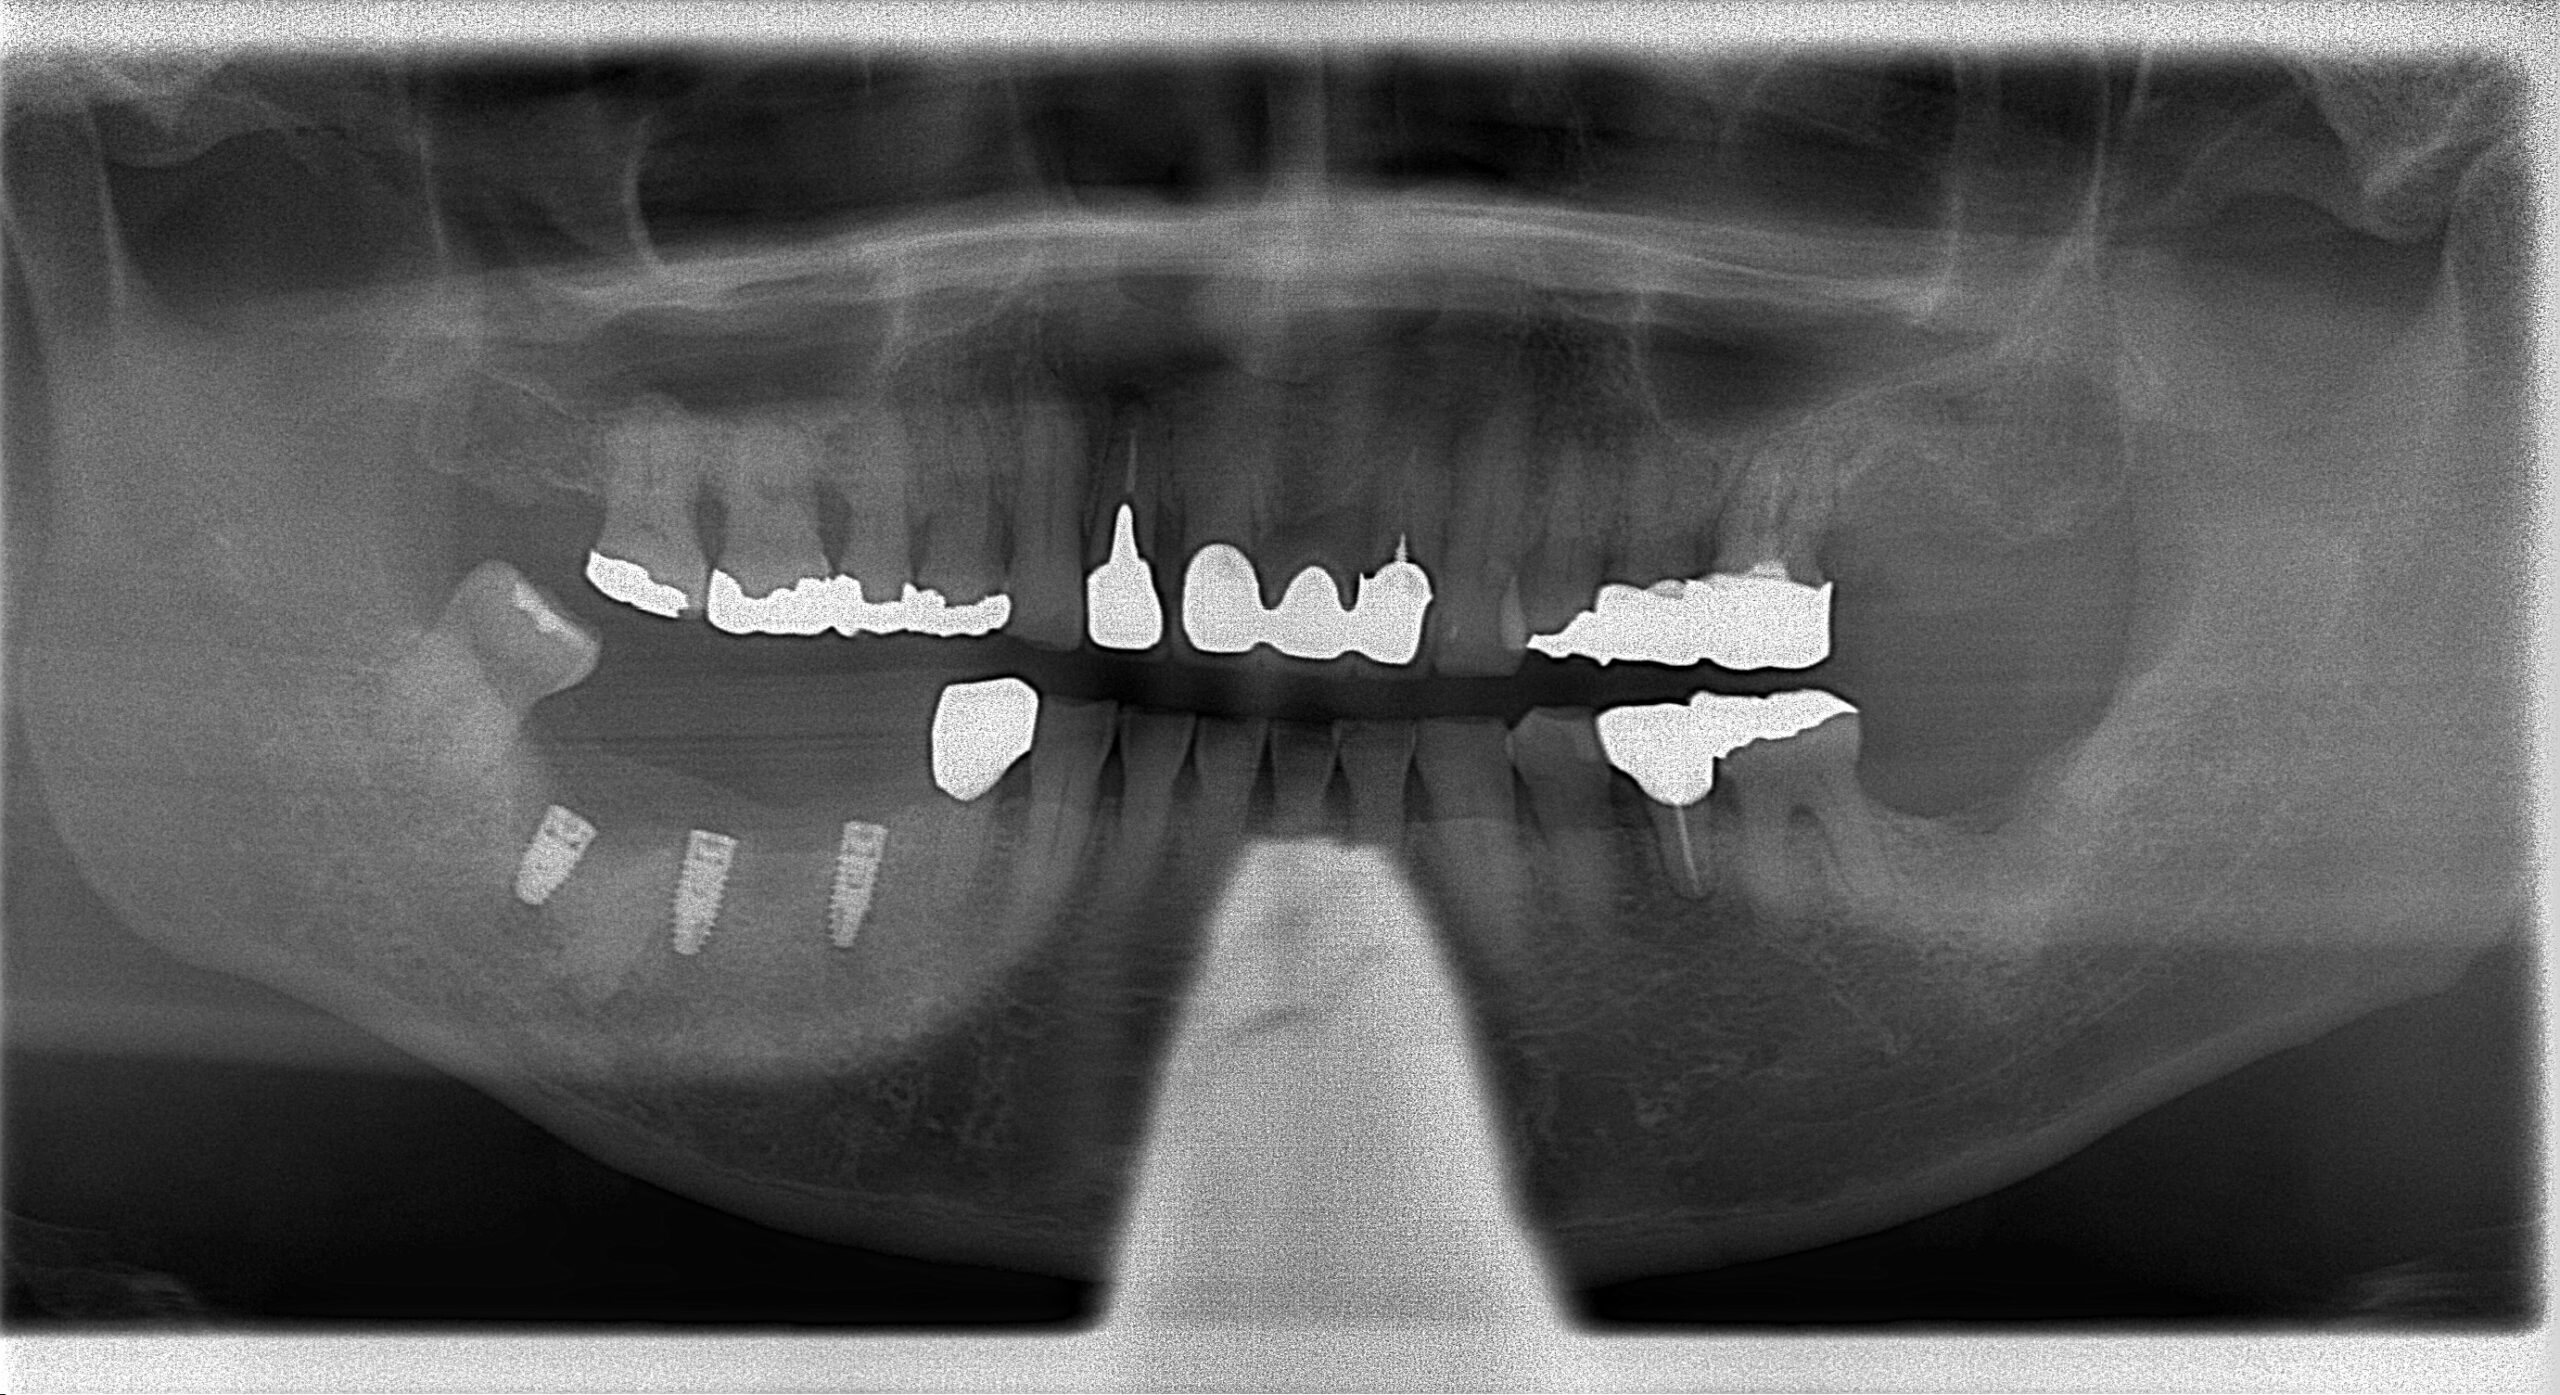

治療前

良い位置にインプラントを埋入することができました。